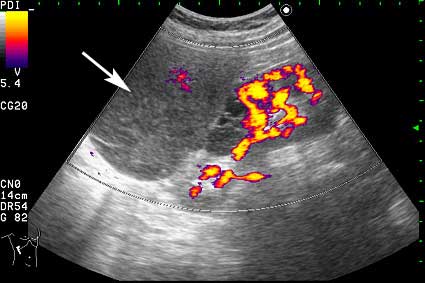

Образование в режиме энергетического доплера.

Что-то прилегает или исходит из почки кпереди...

Нет, это кистоподобное образование, связанное с почкой.

Необычнвя картинка. В голову приходят самые "сумашедшие" предположения (в т.ч. малигнизация кисты, но нет кровотока, нагноившаяся киста, но нет реакции ее стенки; киста с густым содержимым, но отчего оно так загустело?). Просветите нас, пожалуйста.

Почечно-клеточный рак правой почки, кистозная форма.

Но только по густому содержимому кистозного компонента. Стенка тонкая, кровоток не прокрашивается (единичный мелкий срез сосуда в центре образования больше похож на артефакт, а м.б. им и является).

Если бы в этом случае и содержимое было бы более "жидким", вероятность постановки правильного диагноза была бы минимальной.

Я в своем заключении предположил кисту с внутренним кровоизлиянием.

И ошибся.